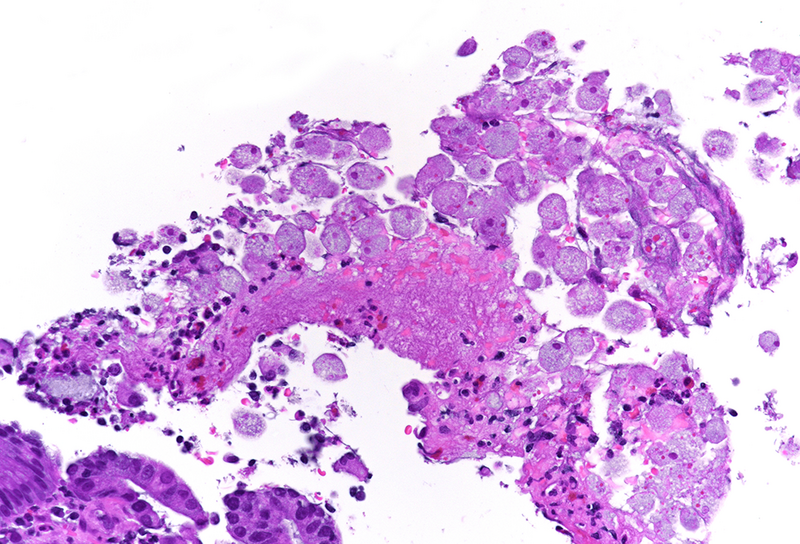

Histology revealed colonic mucosa with preserved architecture. Multiple erosions, crypts with degenerative features and increase of the inflammatory cell infiltrate in the lamina propria, especially granulocytes, were observed (PANEL A-B). On the luminal surface, accompanied by fibrin and debris, multiple organisms with roundish shape, foamy cytoplasm and round, pale and eccentric nuclei were found; some of those have erythrocytes engulfed in their cytoplasm (PANEL C-D); periodic acid-Shiff (PAS) stain highlights these organisms (PANEL E-F), which qualify for diagnosis of amoebiasis.

Histologically, initial lesions show a mild neutrophilic infiltrate, with numerous organisms present at the luminal surface associated with detritus. In advanced disease, ulcers are often deep, extending into the submucosa, sometimes with invasive amoebae within the bowel wall. Entamoeba histolytica has a roundish shape, with foamy cytoplasm and round, pale and eccentric nuclei with an open nuclear chromatin pattern. Within the inflammatory exudate, they may be difficult to distinguish from macrophages; in these cases, histochemical and immunohistochemical stains may be performed: amoebae are trichrome- and PAS-positive and macrophages stain with CD68. It is noteworthy the presence of ingested erythrocytes as pathognomonic feature of this parasite.